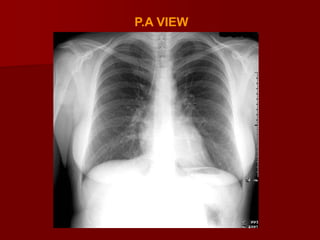

A PA radiograph is obtained with the x-ray traversing the

patient from posterior to anterior and striking the film.

Difference between P.A & A.P VIEW

In PA view

 Clavicles don’t project too high into the apices or

thrown above the apices (more horizontal)

 Heart wont be magnified over the mediastinum

therefore preventing the appearance of

cardiomegaly

 Scapula are away from the lung fields

 Ribs are obliquely oriented in PA view

 Spine and posterior ends of ribs are clearly seen

Why is PA preferred over AP

Reduces magnification of heart therefore

preventing appearance of cardiomegaly

 Reduces radiation dose to radiation sensitive

organs such as thyroid,eyes,breasts

 Visualised maximum areas of lung

 Moves scapula away from the lung fields

 More stable positioning for the patient as they

can hold onto the unit – this reduces patient

movement.

 Compression of breast tissue against the film

cassette reduces the density of tissue around

the CP bases therefore visualizing them more

clearly